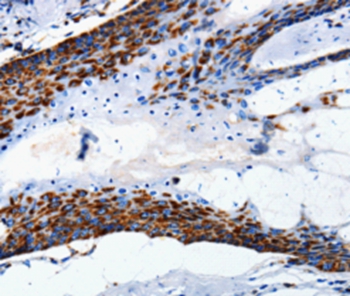

Immunohistochemical analysis of paraffin-embedded Human skin tissue using #36717 at dilution 1/5.